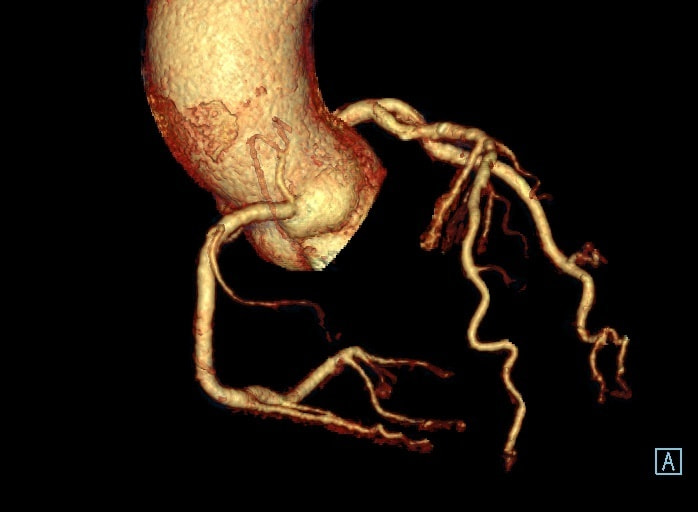

3D画像

撮影した画像から・・・

3D画像は撮影したCT画像を立体的に表示できるため、直感的に解剖学的情報や骨折部位などを把握することができ、診断や治療の助けになっています。出血や脳梗塞などによる緊急IVR検査を迅速に正確に行う為にもとても重要な画像です。